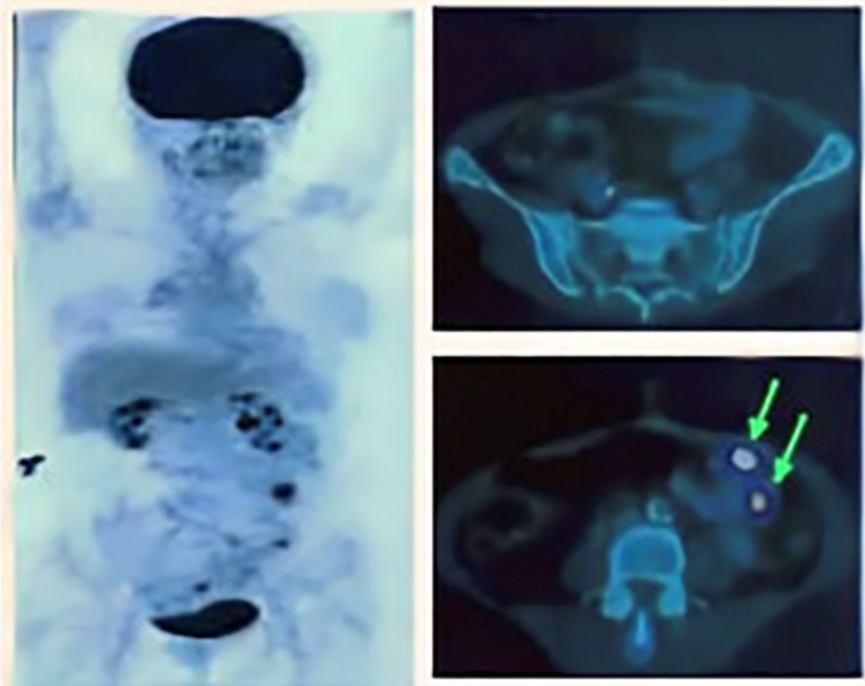

案例显示,印度尼西亚的一位64岁的女性横结肠癌患者,曾长期遭受肠梗阻和血性腹泻的困扰。在接受了横向结肠切除术两个月后,本身初步判断没有出现复发转移的情况。但是由于患者拒绝接受后续的辅助化疗治疗,当6个月后再次进行PET扫描时,显示该患者中结肠和腹膜区域的淋巴结葡萄糖摄取呈阳性,因此医务人员怀疑该区域存在肿瘤组织的复发。

图源参考文献[1] PET-CT扫描后患者部分结肠组织呈阳性

经过两个周期的NK细胞治疗后,再次对患者进行PET扫描随访时,病灶区域免疫相关的不良反应消失了。不仅如此,患者日常生活也恢复正常,直到目前仍没有出现局部复发的迹象和症状[1]。

图源参考文献[1] 接受NK细胞疗法后,免疫相关的不良反应消失